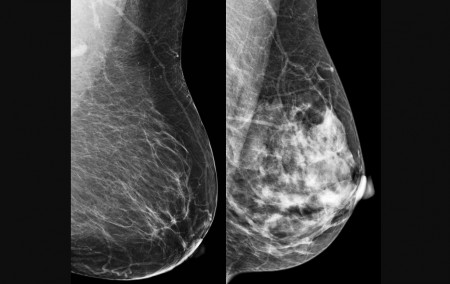

O trabalho foi publicado nos anais do 38º International Symposium on Computer-Based Medical Systems (CBMS), do Institute of Electrical and Electronics Engineers (IEEE). Nele, os autores descrevem uma rede neural híbrida que combina camadas quânticas com camadas clássicas, utilizando uma abordagem conhecida como “quanvolutional neural network” (QNN). O modelo foi aplicado a imagens de mamografias e ultrassonografias com o objetivo de classificar lesões como benignas ou malignas.

O câncer de mama foi escolhido como alvo para teste do modelo computacional porque é o tipo mais comum entre mulheres no mundo, com 2,3 milhões de casos e 670 mil mortes registradas em 2022. A detecção precoce é crucial para aumentar as chances de cura e sobrevida. No entanto, métodos tradicionais, como a mamografia, dependem fortemente da interpretação humana, o que pode levar a variações no diagnóstico. “Apesar de ser teoricamente simples de acompanhar, a mamografia ainda é um exame cuja interpretação depende muito do profissional que realiza o procedimento”, diz Papa.

No estudo, as informações codificadas nos qubits foram pixels das imagens de mamografia e ultrassonografia. Às vezes, um pixel apenas; às vezes, mais de um. O modelo foi testado com duas bases de dados: BreastMNIST (com imagens de ultrassonografia) e BCDR (com mamografias segmentadas). Mesmo utilizando um circuito com apenas quatro qubits, a rede híbrida obteve desempenho competitivo. No melhor caso, alcançou 87,2% de acurácia no conjunto de teste e 86,1% no de validação. “A ideia foi criar uma arquitetura que poderá ser utilizada e aprofundada em outros estudos”, comenta Rodrigues.